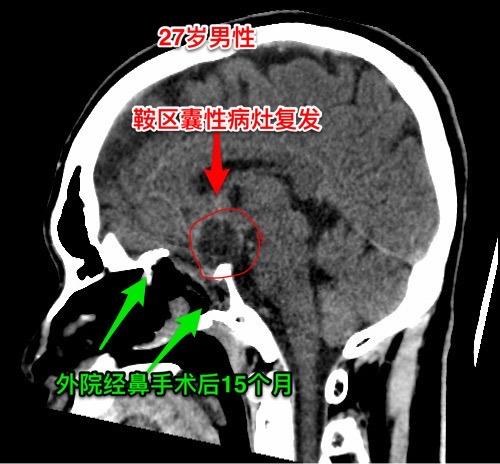

第一次经鼻手术后诊断为颅咽管瘤,可靠吗?27岁广西壮族自治区人,自幼视...